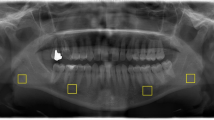

Calcification and resorption foci (“CaR,” qualitative parameter) (Fig. 3).

In patients of the experimental group, more CaR foci (experimental N = 30 (73.2%) patients vs. healthy control N = 24 (58.5%) patients) could be found. The difference between the two groups was not statistically significant (p = 0.244). In Fig. 3 ectopic calcifications are illustrated in the region of the parotid gland (A), tonsillar region (B), ligamentum stylohyoideum (C + D), and the facial artery (E).

From a pathophysiological point of view and as mentioned before, SHPT leads to an imbalance of calcium and phosphate in the blood, resulting in changes to the mineral metabolism and mineral deposition in the form of tonsilloliths, calcified lymph nodes, or ossification of the styloid ligaments. However, we found that those patients with SHPT who had ossifications had this particularly pronounced. In some patients, the mineralization was so pronounced that it could be detected in the vessels as atherosclerosis (Fig. 3E), which as a cardiovascular disease represents the main cause of death in this population [20, 21]. With the radiological experience to recognize these findings in combination with the necessary internal medicine experience, dentists represent an essential aid to patient education and sensitization to prophylaxis to extend lifetime. Although in case of an accidental detection of atherosclerotic plaque in a cervical vessel direct prophylaxis is not completely possible by a dentist, the dentist could enter a new competence area which addresses raising the patient’s awareness of the potential disease as well as the initiation of further diagnostic (e.g., imaging diagnostics like ultrasound diagnostics) and therapeutic steps by consultation with a general practitioner.